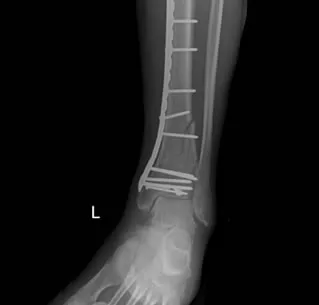

Stap 2: Operatie: zodra de zwelling voldoende is afgenomen (meestal na 1 à 2 weken) volgt de definitieve operatie. De orthopedisch chirurg opent de enkelregio en reconstrueert de gebroken botstukken van het scheenbeen. Deze worden vastgezet met platen en schroeven (osteosynthese). Ook een eventueel gebroken kuitbeen wordt tijdens de operatie vastgezet.

Een pilonfractuur is een complexe breuk in het enkelgewricht die gespecialiseerde behandeling vereist. Meestal is een operatie met platen en schroeven nodig (vaak na een fase van tijdelijke fixatie met een externe fixateur). Een goede revalidatie is cruciaal voor een optimaal resultaat. Ondanks de ernst van deze breuk is het in veel gevallen mogelijk om nadien weer te kunnen stappen en dagelijkse taken te hervatten, al blijft zwaar belasten van de enkel soms moeilijk.